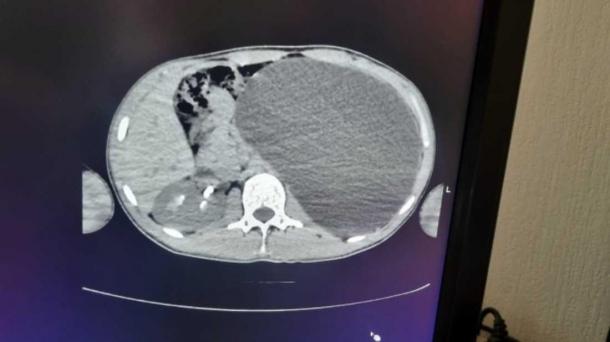

В Новосибирске врачи спасли 17-летнего юношу, который сам не подозревал о смертельной опасности. На плановом медосмотре перед трудоустройством молодому человеку сделали УЗИ и обнаружили, что левой почки фактически не видно — вместо нее в брюшной полости находилось огромное образование. Пациента экстренно направили в детскую городскую клиническую больницу № 1, где диагноз подтвердился: гидронефроз в запущенной стадии.

Как выяснилось, патология развивалась годами бессимптомно. Орган, лишенный возможности нормально выводить мочу, раздулся до размеров пятилитровой бутылки и занял почти весь живот, сместив соседние органы. Почка превратилась в тонкостенный мешок с жидкостью, который мог лопнуть при любом неловком движении или ударе, что привело бы к фатальному исходу. При этом сам подросток чувствовал себя абсолютно здоровым и никогда не жаловался на боли.